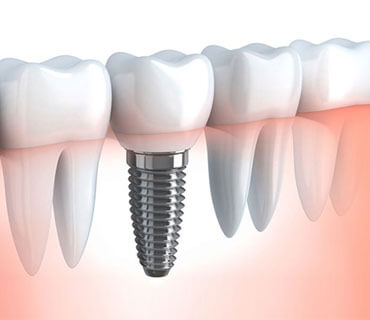

Dental Implants

When teeth are lost because of disease or an accident, dental implants may be a good option

- Same Day Implants

- Implant Bridges

- Dental Implants

- All on 4

- Implant Dentures